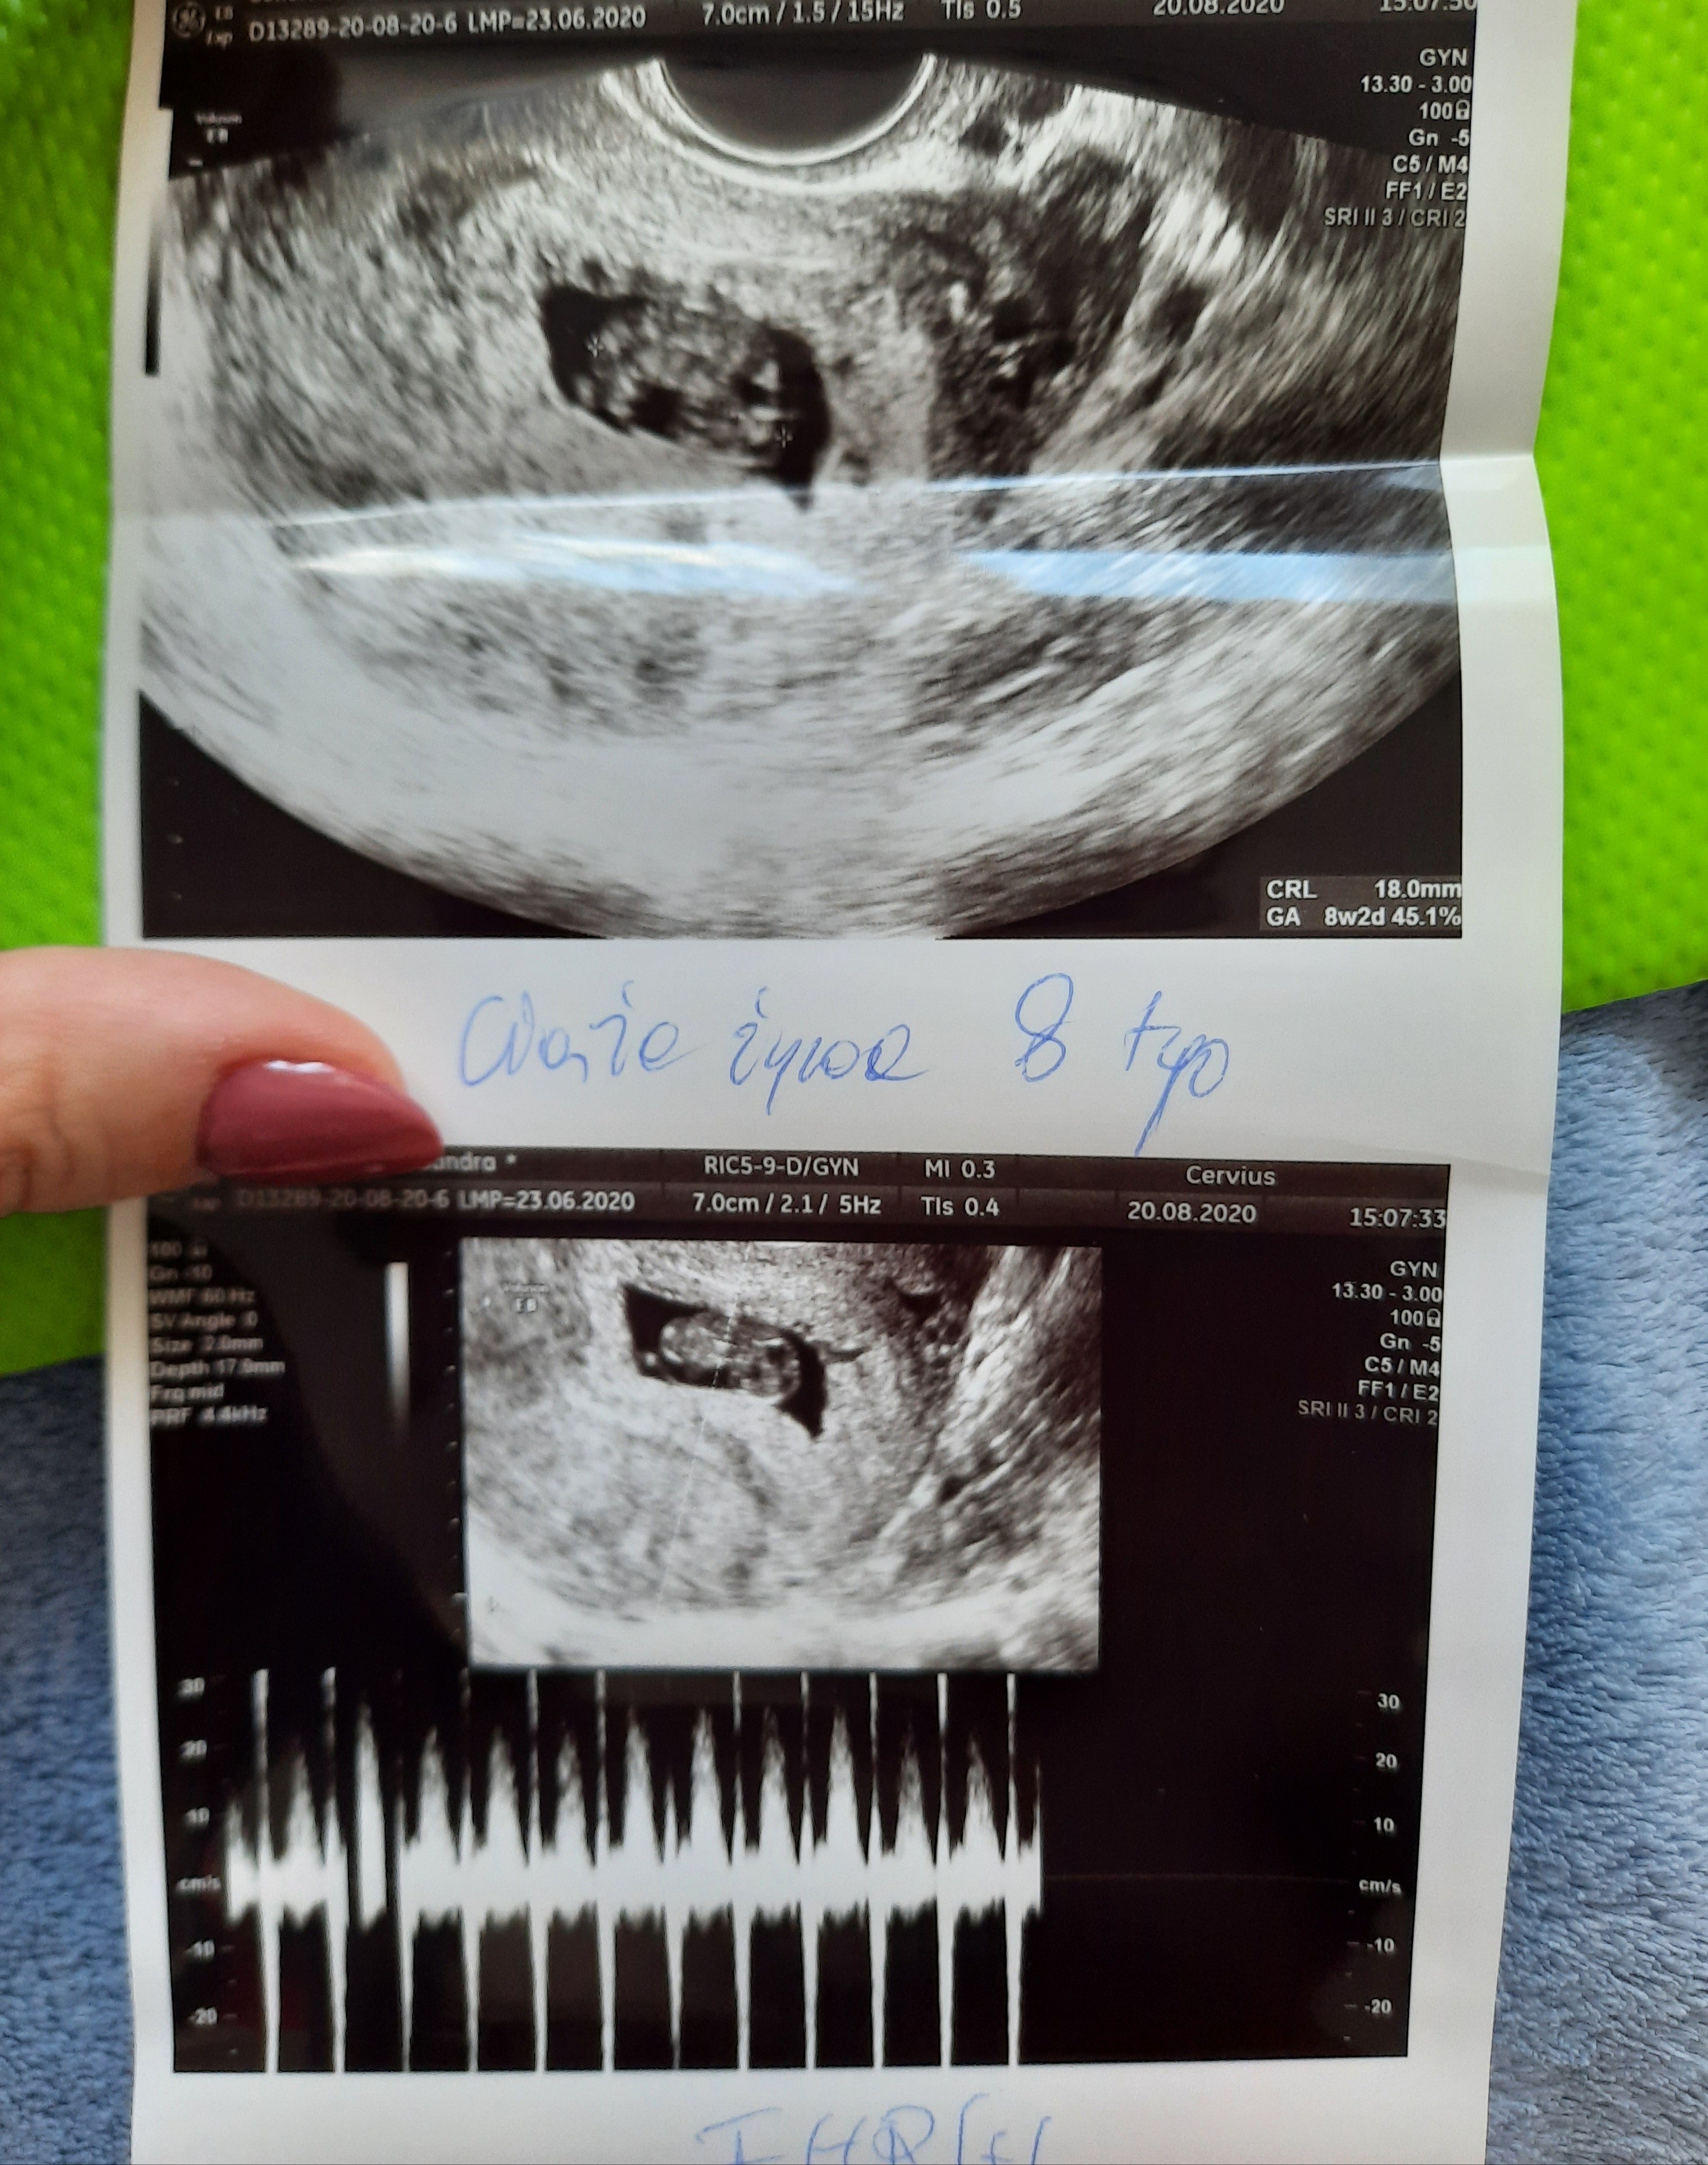

gratulacje ze tak fajnie to się ułożyłoWrocilam od lekarza dzidzius ma 18mm 8+2 ,wszystko dobrze się rozwija moge trochę odetchnąć kolejna wizyte mam teraz dopiero za miesiac 15.09.

Suuuuuper!! Bardzo się cieszę [emoji7][emoji7]Wrocilam od lekarza dzidzius ma 18mm 8+2 ,wszystko dobrze się rozwija moge trochę odetchnąć kolejna wizyte mam teraz dopiero za miesiac 15.09.